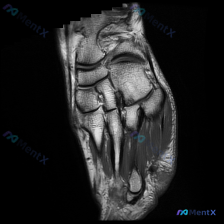

看到一份很有代表性的读片病例,提问是针对「软骨异常」的观察,整理了完整分析思路分享给大家。 一、基础影像信息 这是一张足部MRI的冠状位T1加权图像(一开始误判为矢状位,这里先纠正),图像信噪比良好,解剖结构清晰,没有明显伪影。T1WI序列上骨髓脂肪呈高信号,皮质骨呈低信号,符合序列特征。 二、系统...

整理了一个挺有启发的病例,这里的关键矛盾点很容易被忽略,跟大家分享一下思路: 病例基本情况 - 患者:37岁男性 - 背景:6个月前高速车祸,因严重头部损伤在ICU住了4个月 - 主诉:现已转康复医院,左足疼痛,负重和尝试行走时明显加重 影像资料(左足正/斜/侧位X光)分析 影像报告的描述其实偏“乐...